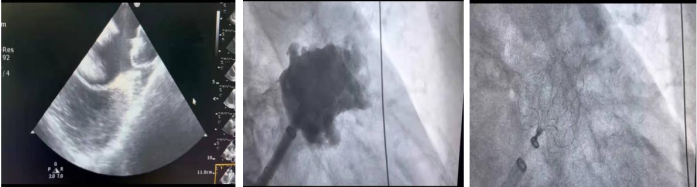

云中二院讯(通讯员 陈昌国)1月9日,医院首例房颤一站式手术(房颤导管消融+左心耳封堵)在DSA室经过孟照辉教授团队的指导顺利完成。

该患者为一位68岁女性,房颤多年,心脏增大,有脑梗死病史,3年来反复心前区不适,胸闷气短,生活质量严重下降。入住我院神经-心血管科治疗后,科主任侯春香主任医师和心血管组负责人陈昌国副主任医师评估了患者的血栓及出血风险,与患者及家属充分沟通交流。开展了本次房颤射频消融+左心耳封堵一站式手术。术后12小时,患者即可下床活动,胸闷心慌等症状明显改善。

房颤治疗的首要目标是恢复正常窦律和预防血栓。导管消融是房颤恢复窦律的最有效措施,而经皮左心耳封堵是预防血栓的有效措施。房颤的导管消融+左心耳封堵“一站式”手术,是心血管内科的微创介入手术,在恢复正常节律的同时可大大减少心源性血栓的风险,术后不需要长期口服抗凝药物,避免了高卒中房颤患者长期抗凝治疗带来的出血风险,大大改善预后。